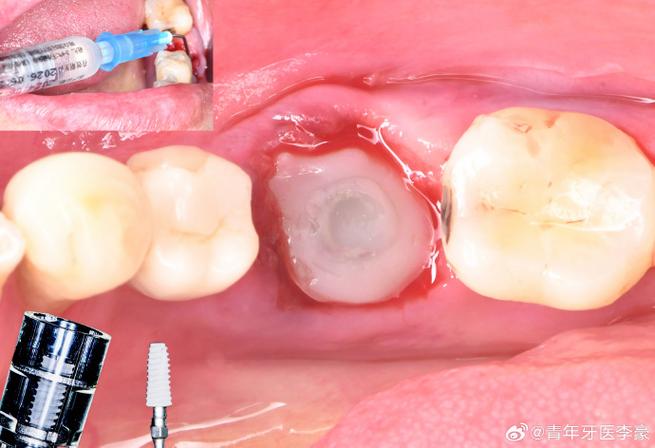

级差备洞的核心是“阶梯式骨增量”,即通过逐级扩孔,形成直径递增、深度可控的锥形窝洞,既保留骨组织支撑力,又为种植体提供初期锚固力,其操作需结合术前CBCT评估骨质、骨量及解剖结构,具体步骤如下:

- 逐级备洞:以直径2.0mm的先锋钻定位窝洞中心,保持转速<800rpm,冷却液流量>50ml/min;后续每级扩孔钻直径递增0.3-0.5mm(D1类骨质)或0.5-0.8mm(D4类骨质),深度逐级增加2-3mm,直至达到种植体植入所需深度(通常为种植体长度的2/3)。

- 种植体植入:将种植体旋入窝洞,确保扭矩值达到35N·cm以上(D4类骨质可适当降低至25N·cm),避免过度用力导致骨裂。